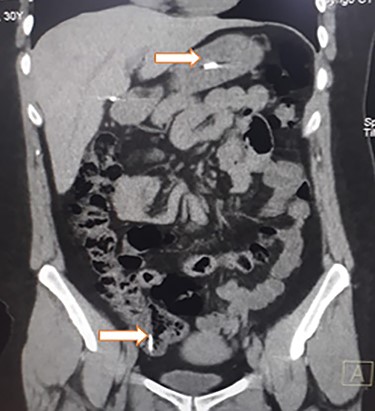

Her postoperative period was uneventful (Fig. 4); liquid diet was started on the second postoperative day and was followed by a full diet. A complete psychiatric evaluation was requested before discharge, and she was kept on close surveillance for a year. On follow-ups, the patient is doing well and is still under psychiatric surveillance and anti-depressive medication.

Abdominal X-ray on the postoperative period without any razor blades.